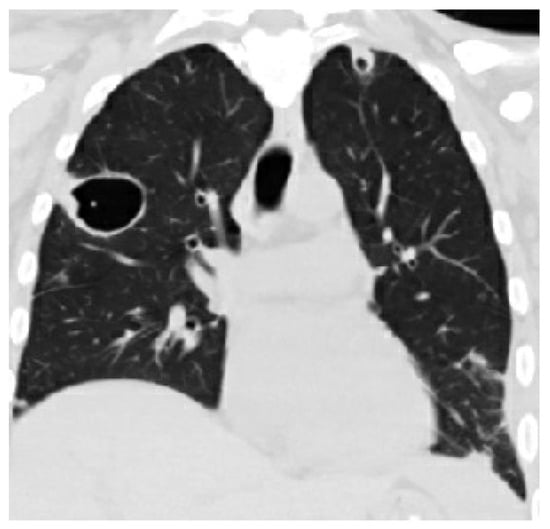

Radiological findings continue to be a mainstay in the diagnosis of necrotizing pneumonia. However, chest X-rays often are not sensitive enough to make the definitive diagnosis of necrotizing pneumonia or to differentiate it from other causes, such as lung abscesses. Bulging fissures may be an early radiographical sign, indicating the extensive inflammation that occurs [3]. A CT with contrast is the optimal imaging modality as it enables the appreciation of areas with low attenuation and decreased enhancement, which are compatible with necrotizing lesions. In contrast to pulmonary abscesses or gangrene, which tend to be isolated to one lobe, necrotizing pneumonia more frequently is multi-lobar in nature and has more extensive airway disease [3,17]. The right middle and lower lobes are most commonly affected in imaging [25]. The presence of micro-abscesses can be used to distinguish necrotizing pneumonia from other conditions causing parenchymal lucency. Significant overlap continues to exist between radiographical findings of necrotizing pneumonia and pulmonary gangrene. Many sources use the extent of lobe involvement as a distinguishing feature, with the term pulmonary gangrene being used when greater than 50% of the lobe is affected [26]. (See Figure 2).

Figure 2.

CT scans of a patient with necrotizing pneumonia and progression through time, with row (D) representing images after the completion of treatment. The time between images in row (A) and row (D) is six weeks. Row (B,C) represent CTs that were taken in between the time of row (A) and row (D), showing the progression of improvement.